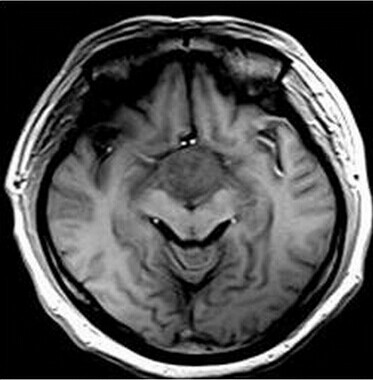

第三脑室脊索样胶质瘤

患者:男,50岁,记忆力下降1月余,双眼视力下降,反应减慢。

【正确答案】D 胶质瘤(第三脑室脊索样胶质瘤)

第三脑室脊索样胶质瘤的特征性表现是:

(1)见于成人,边界清楚,位于第三脑室前部;

(2)T1WI上为低信号,T2WI上呈明显高信号;

(3)增强后明显强化;

(4)肿块累及视交叉及下丘脑,但不浸润周围脑实质。